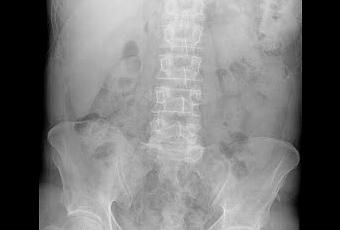

Lóbulo Hepático de Riedel

El lóbulo hepático de Riedel es una variante anatómica en la cual hay una prolongación hepática derecha en forma de lengüeta o punta de lanza que abarca el flanco derecho y puede llegar incluso hasta la cresta iliaca. El lóbulo de Riedel puede ser un hallazgo al examen físico y podría confundirse con una hepatomegalia. También aparece descrito en Rx de abdomen como en la imagen del artículo o durante la ecografía abdominal.En pacientes sanos el diagnostico es muy fácil pero cuando hay enfermedad o alteraciones de la función hepática la presencia del lóbulo de hepático de Riedel puede llevar a realizar pruebas innecesarias ante la sospecha de un crecimiento hepático. Lo que habitualmente nos ayuda a diferenciarlo es su forma característica.

No hay problemas de la salud asociados a tener una variante hepática de Riedel a excepción del hecho de tener parénquima hepático por debajo del reborde costal, sin protección, podría favorecer hematomas hepáticos en casos de traumatismos abdominales.